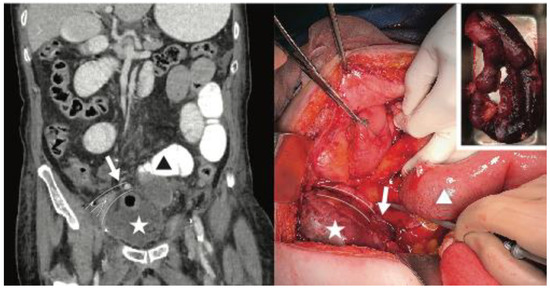

Incarcerated Internal Hernia Posterior to the Iliac Vessels After Uncomplicated Radical Cystectomy

Sparanese, S.; Chehroudi, C.; Black, P.C. Incarcerated Internal Hernia Posterior to the Iliac Vessels After Uncomplicated Radical Cystectomy. Soc. Int. Urol. J. 2023, 4, 71-72. https://doi.org/10.48083/ZJNE2733